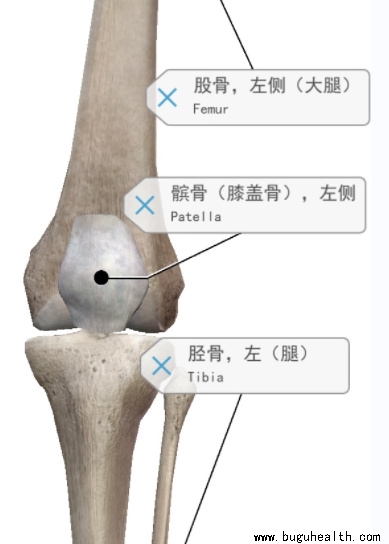

- 布骨医学科普:带你了解什么是髌骨脱位! BuGuRMC布骨康复医疗中心 ,2023-06-25

- 髌骨是连接大腿和小腿的一个小骨头。髌骨脱位意味着髌骨与其正常位置不同,其通常会向膝盖外侧偏移。这种情况可能会导致关节软骨的损伤并引起旁侧组织的疼痛和肿胀。那么为什么会发生髌骨脱位? 髌骨脱位通常是由过度的运动,或者软组织和肌肉不平衡引起的。.....